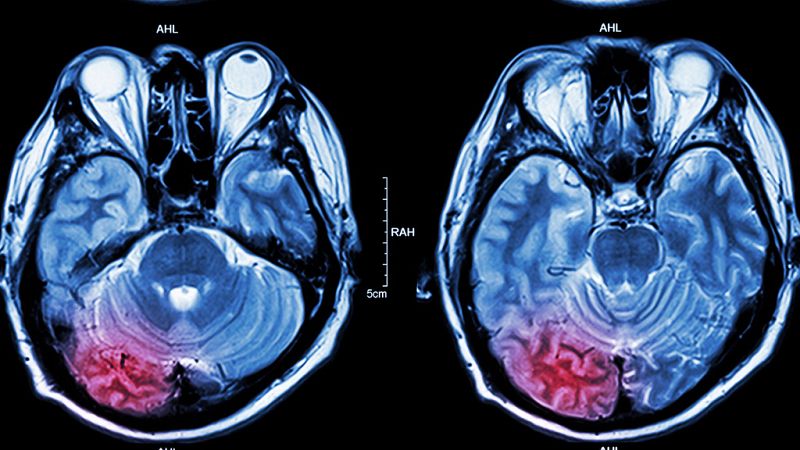

Los infartos cerebrales son la primera causa de muerte de las mujeres en España. Una de cada cinco mujeres sufre un accidente cerebrovascular en algún momento de su vida y en España más de 16.000 mueren al año por ello, 4.000 más que entre los hombres. ¿Por qué las mujeres son más proclives a sufrir un ictus?

Hombres y mujeres comparten los factores de riesgo de ictus, pero ellas padecen más patologías de vasos sanguíneos y arterias porque "tienen mayor sensibilidad biológica a sufrir un daño cerebral por cualquier estímulo, como por ejemplo el tabaco".

"Cualquier enfermedad que tenga un impacto sobre las arterias tiene un efecto más rotundo en las arterias de las mujeres", incide Castro y sus consecuencias varían dependiendo de la zona que ha afectado al vaso infartado, del tiempo que ha estado el cerebro sin recibir sangre y del daño que ha producido.